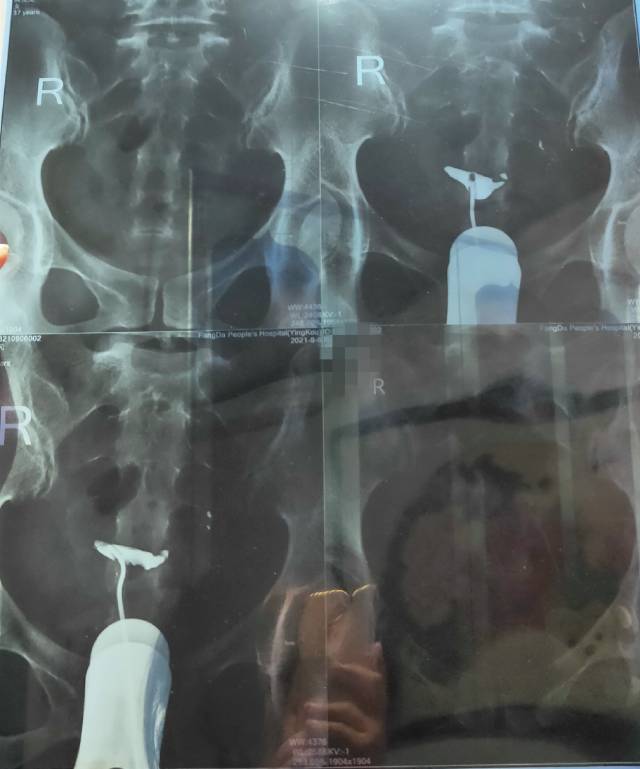

37周岁,这种情况好治疗吗?怎么治疗方法好呢?

输卵管造影双侧不通,可以做试管,如果非常想自己试孕,要做宫腹腔镜检查,继续导丝疏通输卵管,如通畅了马上卵泡监测指导受孕。

你的年龄结合你的输卵管不通建议直接试管助孕,年龄大了等不起了,再就是你这种完全不通做宫腹联合手术效果也不好,还是尽早试管助孕吧。